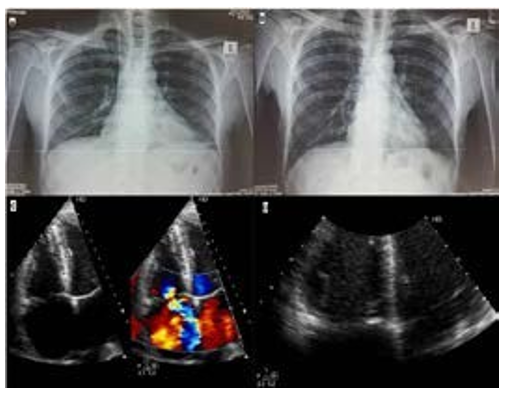

Chest X-ray was done a day later after central venous catheter insertion and astonishingly we found the introducing guide wire left inside his heart starting from the right internal jugular vein towards the right atrium and ventricle making a loop inside the pulmonary artery then down through the inferior vena cava towards the hepatic vein. The lost wire was retrieved blindly without fluoroscopic guidance and follow-up X-ray showed no residual wire parts, then he was referred to us for echocardiography and we found severe tricuspid valve regurgitation with no signs of chronicity with perforation of the anterior leaflet, no visible vegetations or thrombi, right and left ventricular systolic and diastolic functions were completely normal and no pericardial effusion.

Figure 1: A: Chest X-ray showing the CVC insertion wire left inside the right side of the heart making a loop in the pulmonary artery then down to the hepatic veins. B: Chest X-ray after removal of the lost wire. C: 2D Echocardiography with color compares showing the severe tricuspid valve regurgitation. D: 2D Echocardiography for a zoom image on the tricuspid valve during diastole showing the perforated leaflet.